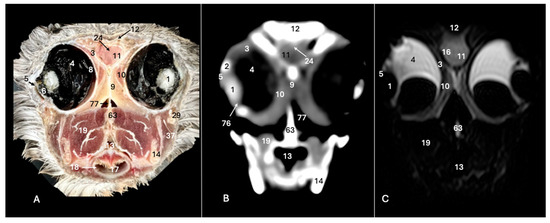

3.1. Anatomical Sections

3.2. Computed Tomography (CT)

3.3. Magnetic Resonance Imaging (MRI)